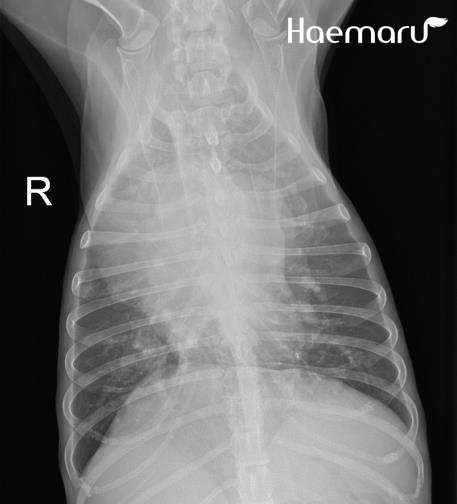

입원 처치 후 폐야 개선 소견 확인